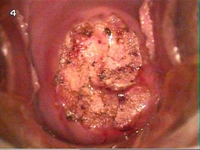

Rahim ve Yumurtalık Ameliyatı: Riskler ve SonrasıRahim ve yumurtalık ameliyatları, kadın üreme sağlığını etkileyen çeşitli durumların tedavisinde sıklıkla başvurulan cerrahi yöntemlerdir. Bu ameliyatlar, fibroidler, kistlerin çıkarılması, endometriozis, kanser gibi rahim ve yumurtalıklarla ilgili hastalıkların tedavisi için uygulanabilmektedir. Ancak her cerrahi müdahalede olduğu gibi, bu ameliyatların da belirli riskleri ve sonrasındaki süreçleri bulunmaktadır. Rahim ve Yumurtalık Ameliyatlarının TürleriRahim ve yumurtalık ameliyatları, hastalığın türüne ve ciddiyetine göre farklılık göstermektedir. Genel olarak şu türleri içerir: